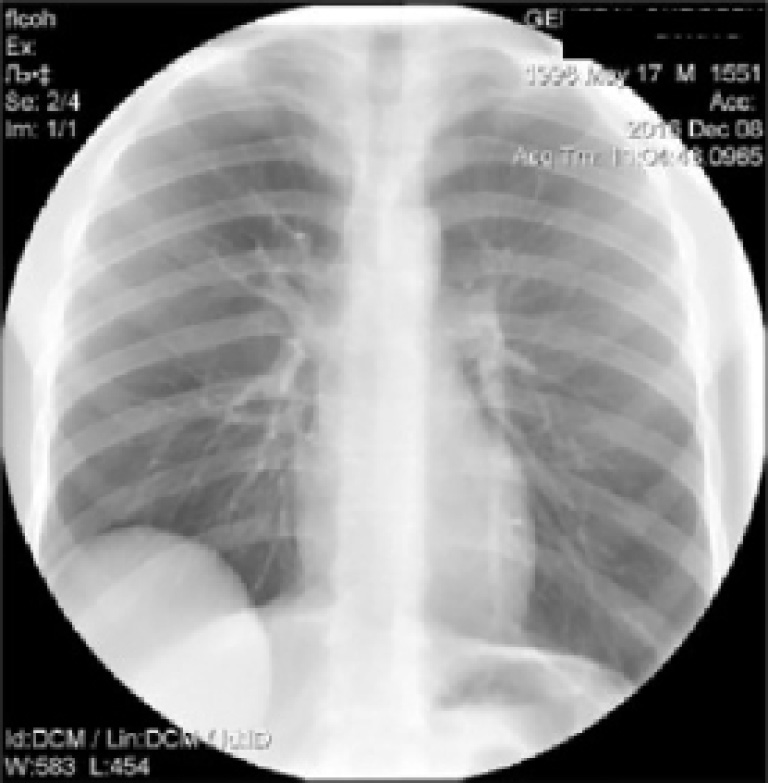

Повторно выполнена рентгенография органов грудной полости в прямой и правой боковой проекциях.

На рентгенограмме органов грудной полости в прямой проекции (рис. 1) в нижних отделах правого легочного поля определяется большое округлое затемнение с четкими ровными контурами.

Рис. 1. Рентгенограмма органов грудной полости пациента Н. в прямой проекции в положении стоя